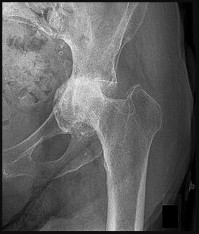

A 38-year-old male presents with right hip pain. He has a history of long-term corticosteroid use for severe asthma. Radiographs demonstrate an area of sclerosis and subchondral radiolucency (crescent sign) in the anterosuperior aspect of the femoral head, consistent with osteonecrosis. According to the modified Ficat and Arlet classification, the presence of a structural subchondral collapse (crescent sign) without narrowing of the hip joint space places him in which stage?

Explanation

The Ficat and Arlet classification is classically used to stage osteonecrosis of the femoral head based on standard radiographs. Stage I has normal radiographs (but positive MRI). Stage II shows cystic/sclerotic changes without subchondral collapse. Stage III is defined by subchondral collapse, which is classically visualized as the 'crescent sign' (subchondral radiolucency indicating mechanical failure of the trabecular bone), but the joint space remains preserved. Stage IV involves secondary osteoarthritis with joint space narrowing and acetabular changes.